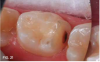

Case 3. This 10-year-old boy was brought to the office for a second opinion regarding restoration of the left primary first molar, which was causing sensitivity (Figure 8). The boy's mother reported that a "tooth-colored filling" had been suggested at another office. The boy was terrified of needle injections and, according to his mother, had required sedation in prior years for restoration of maxillary primary molars. SDF was applied (Figure 9), tooth sensitivity was eliminated, and in 3 months, clinical evaluation and a periapical radiograph confirmed that no other treatment would be needed until the tooth exfoliated (Figure 10 and Figure 11).

Fig 9. SDF applied.

Fig 9

Fig 10. 3 months after SDF application, no additional treatment needed.

Fig 10